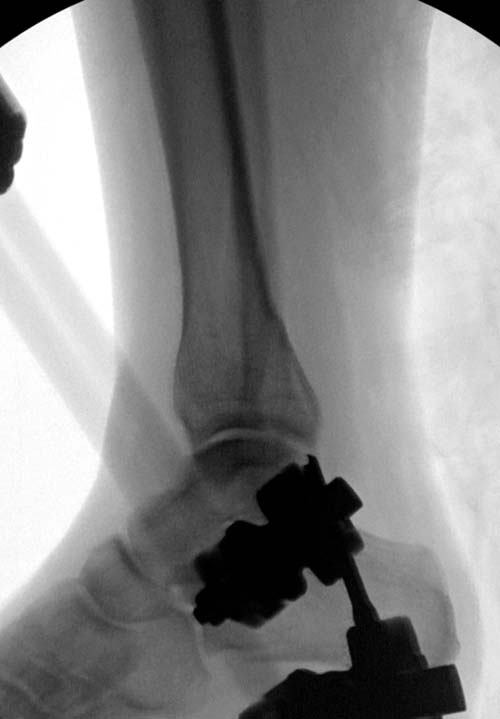

Первый случай, где перелом в результате падения с  небольшой высоты, где

мортиз рентген снимок показал отстутствие укорочения наружной

лодыжки и КТ срезы подсказали направления атаки. После такой фиксации

нет надобности в гипсовой повязке, брейс и через две недели движения в

суставе без нагрузки.